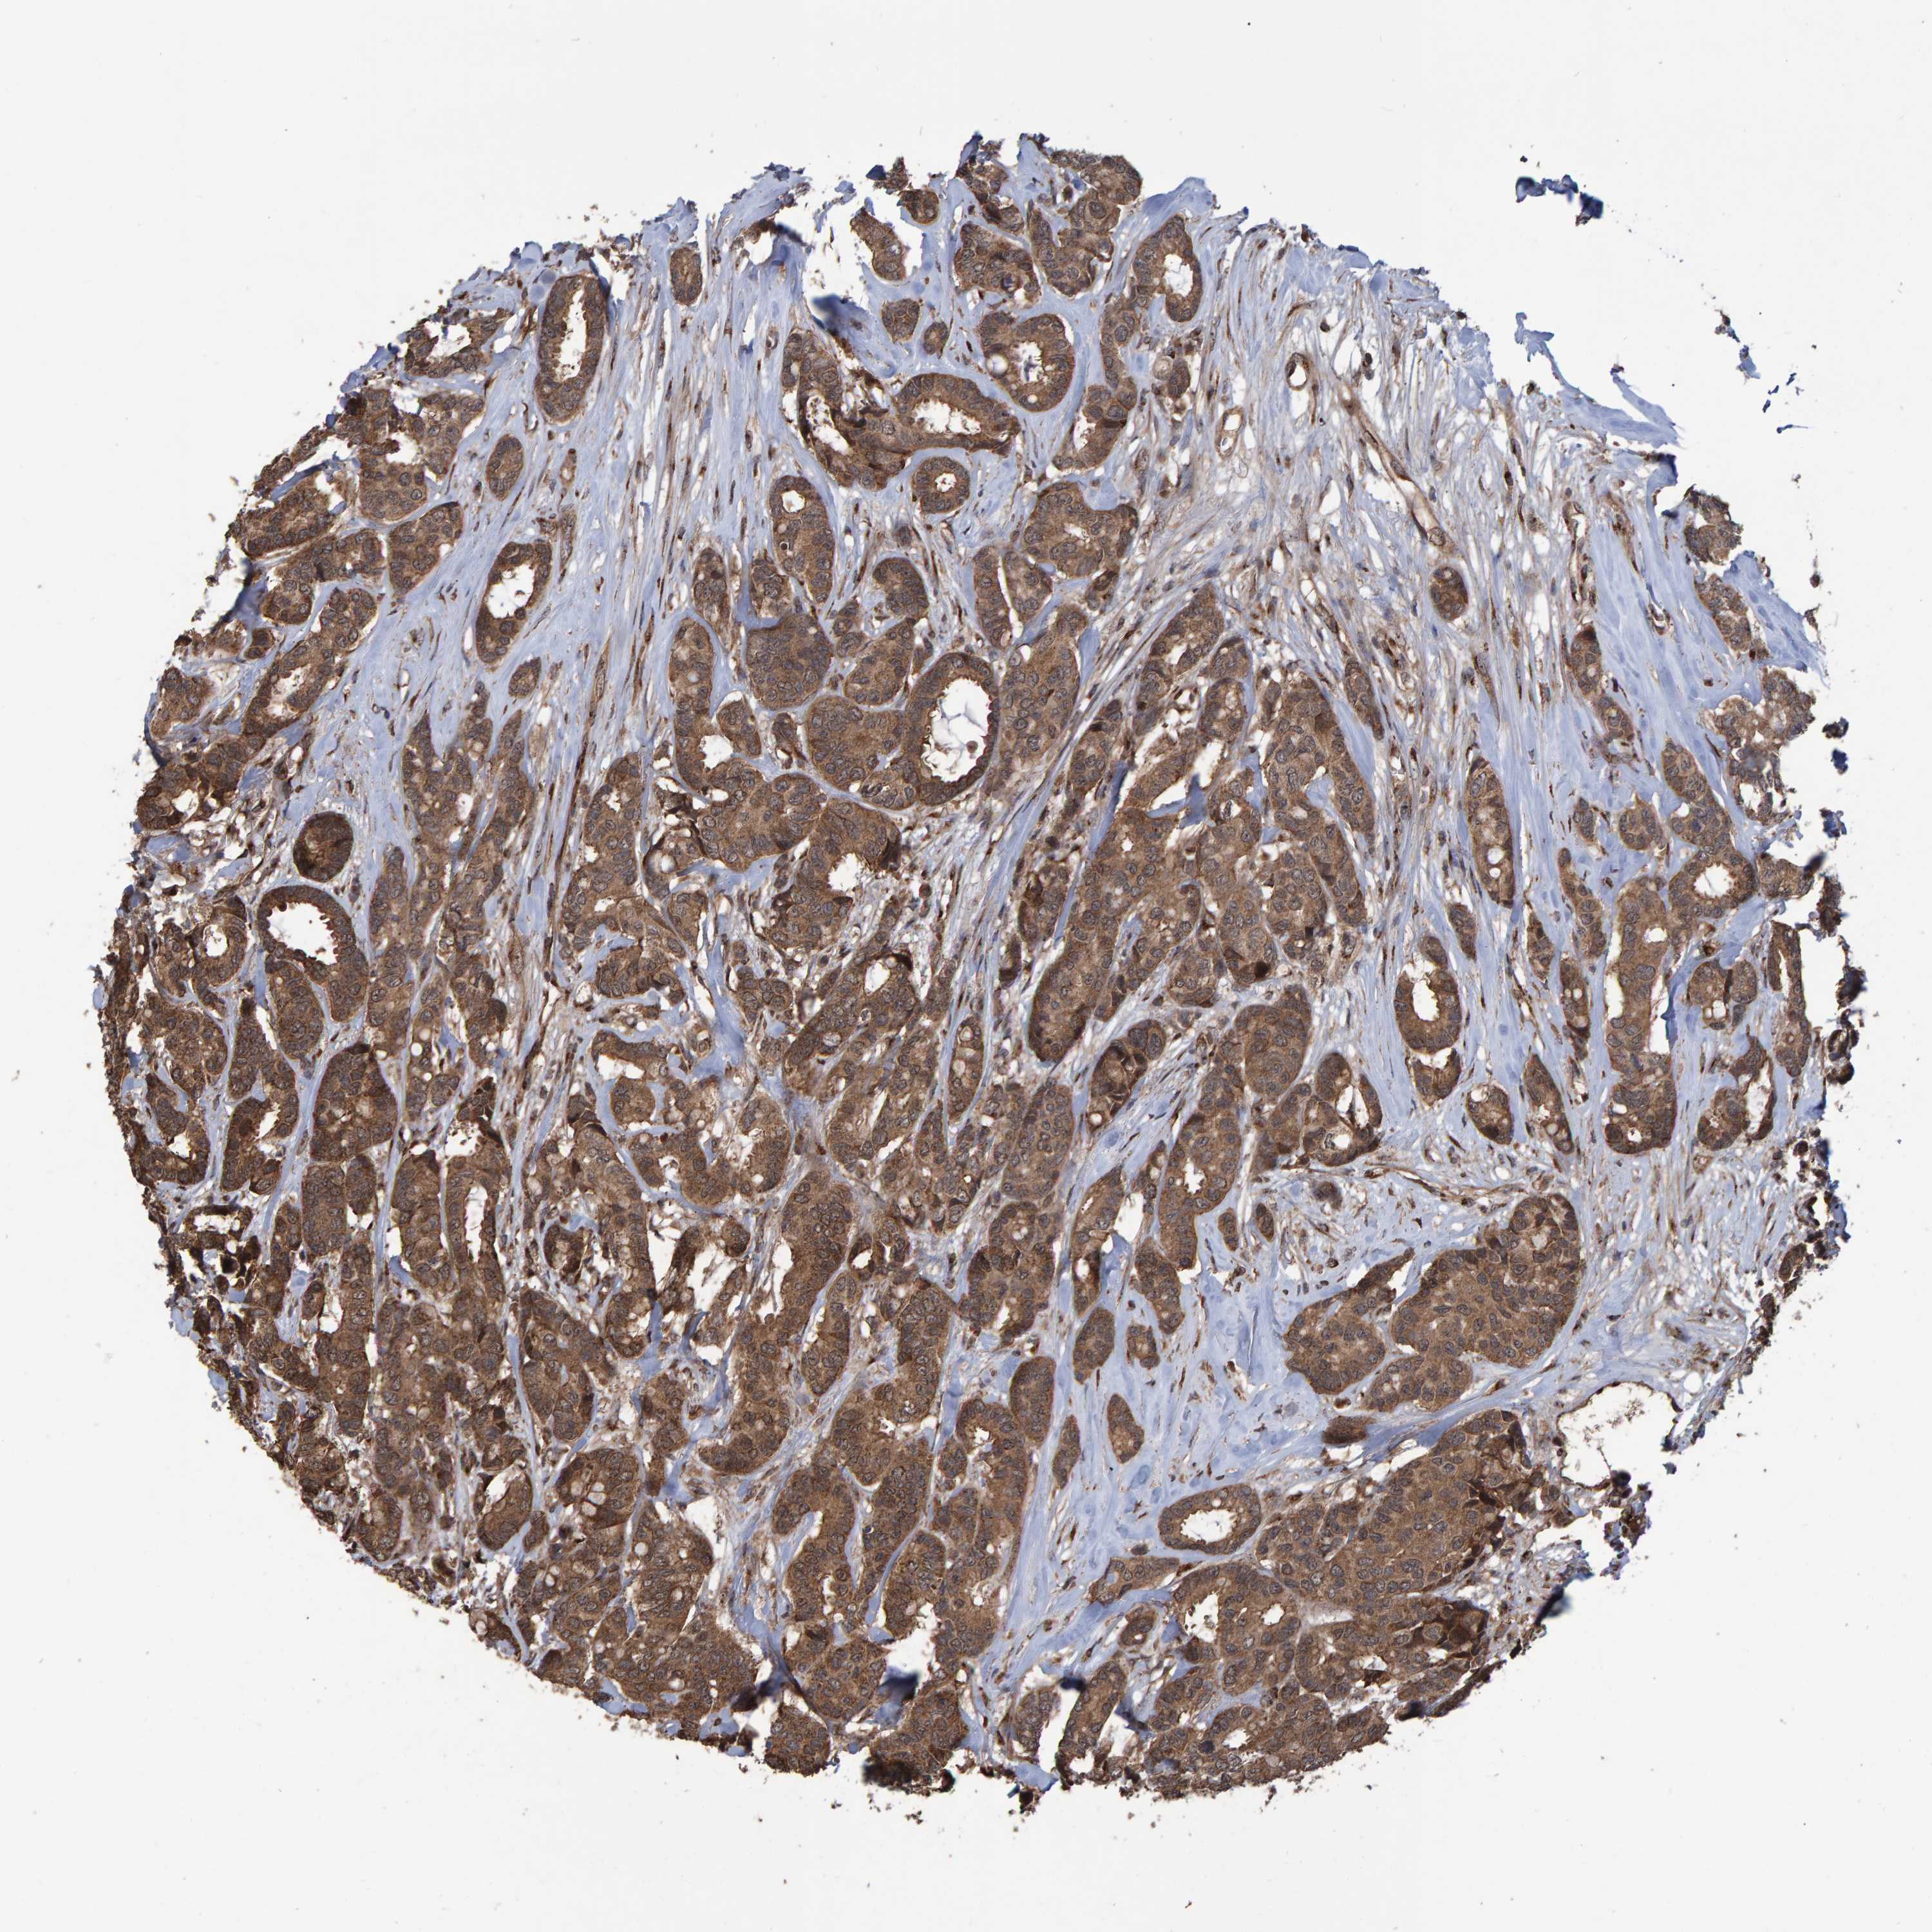

CANCER BREAST CANCER Show tissue menu

BRCA TCGA BRCA VALIDATION PROTEIN EXPRESSION